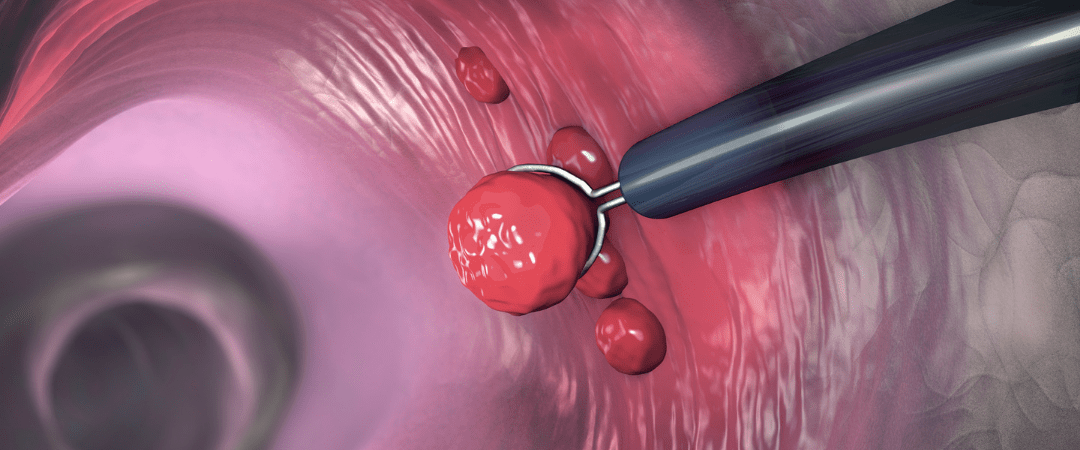

پولیپکتومی یکی از روشهای جراحی است که در آن پولیپهای موجود در سیستم گوارش و کبد برداشته میشوند. این جراحی برای درمان برخی از بیماریهای مرتبط با پولیپها مورد استفاده قرار میگیرد. برخی از موارد معمول برای اجرای پولیپکتومی شامل پولیپهای بزرگ، پولیپهای خطرناک مانند پولیپهای حاوی سلولهای آب بران و پولیپهایی که علائمی مانند خونریزی دارند، است. این جراحی به عنوان یک روش درمانی مناسب برای پولیپهای گوارشی و کبدی شناخته شده است و به بیماران کمک میکند تا بهبود خود را تجربه و از علائم ناراحت کننده پولیپها رها شوند. با انجام پولیپکتومی، پتانسیل برای رشد پولیپهای بیشتر در آینده کاهش مییابد و بیمار میتواند به طور کامل به سلامتی خود بازگردد.

در بعضی موارد، با انجام پولیپکتومی میتوان تشخیص دقیق بیماریهایی نظیر سرطان گوارش و غیره را نیز بررسی کرد. این جراحی همچنین به عنوان روشی تشخیصی نیز به کار میرود که به کمک آن میتوان نواحی مورد نیاز را بررسی کرده و آزمایشهای لازم را انجام داد. علاوه بر این، با انجام پولیپکتومی میتوان مطمئن شد که پولیپهای خطرناک و شایع مانند پولیپهای آدنوماتوز به طور کامل برداشته شدهاند و هیچ علامتی از آنها باقی نمیماند. در نتیجه، این جراحی میتواند برای حفظ سلامتی بیماران بسیار مفید و اثربخش باشد.

پیش از جراحی یک سری تستها و بررسیها برای تشخیص و بررسی پولیپهای گوارشی صورت میگیرد. این بررسیها شامل آندوسکوپی (معاینه درونی سیستم گوارشی با استفاده از یک لوله نازک انعطافپذیر که دارای دوربین است) و بیوپسی (برداشتن نمونههای بافتی برای آزمایش) است.

جراحی

در مرحله جراحی، پولیپ از داخل گوارش یا کبد برداشته میشود. این جراحی میتواند به صورت باز یا به صورت لاپاراسکوپیک (استفاده از لوله نازکی که دوربین و ابزار جراحی را به داخل گوارش یا کبد میبرد) انجام شود. هدف از جراحی برداشتن پولیپ، برطرف کردن مشکل و جلوگیری از پیشرفت بیشتر پولیپ و تغییرات آن به سرطان است.

جراحی برداشتن پولیپهای گوارشی تاثیرات متعددی بر سلامت گوارش دارد. این جراحی میتواند به پیشگیری از تغییرات پولیپ به سرطان کمک کند. همچنین، با برداشتن پولیپها، عوارض خطرناکی مانند خونریزی و التهاب در محل پولیپ قبل از جراحی، بهبود مییابد. این موضوع باعث میشود بیماران بتوانند به طور طبیعی و بدون مشکلات از گوارش خود استفاده کنند.